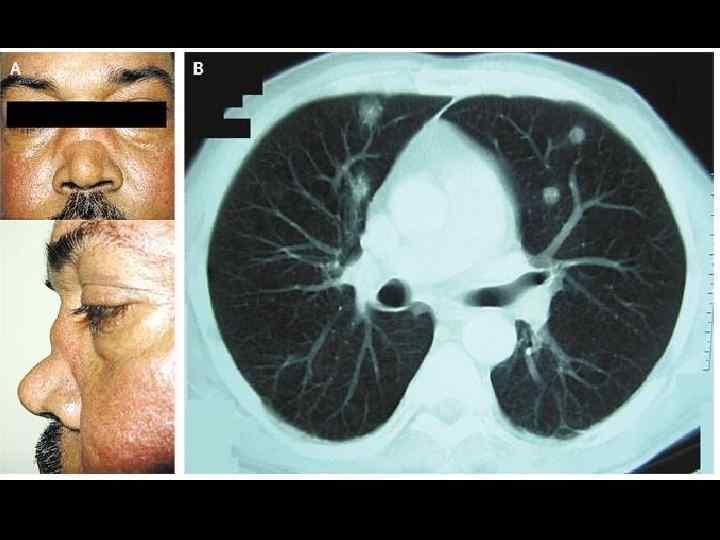

При отсутствии адекватного лечения болезнь Вегенера может привести к летальному исходу в течение 6-12 месяцев. Локальная форма заболевания может вызвать различные проблемы с глазами, ушами, носовой полостью и ее пазухами. В случае генерализованной формы основное поражение наблюдается в легких и почках. Развивается легочный гранулематозный васкулит, в легких образуются гранулемы, которые нередко распадаются, формируя кровоточащие каверны.

- Изменение формы носовых костей – это следствие гранулематоза, воспалительных процессов и некроза тканей.

- Кровохарканье. При распространении заболевания на легкие образуются полости, которые могут начать кровоточить при разрушении.

При генерализованной форме также может пострадать орган зрения: слезные протоки могут закупориваться, что приводит к воспалительным заболеваниям глаз. Наличие множества гранулем может привести к полной потере зрения. Кроме того, возможно развитие тромбоза глубоких вен, трофических язв на ногах и гангрены пальцев и стоп.

Инструментальные исследования, такие как рентгенография грудной клетки, компьютерная томография (КТ) и магнитно-резонансная томография (МРТ), могут помочь визуализировать изменения в легких, почках и других органах. Эти методы позволяют выявить гранулемы, инфильтраты и другие патологии, характерные для болезни Вегенера.